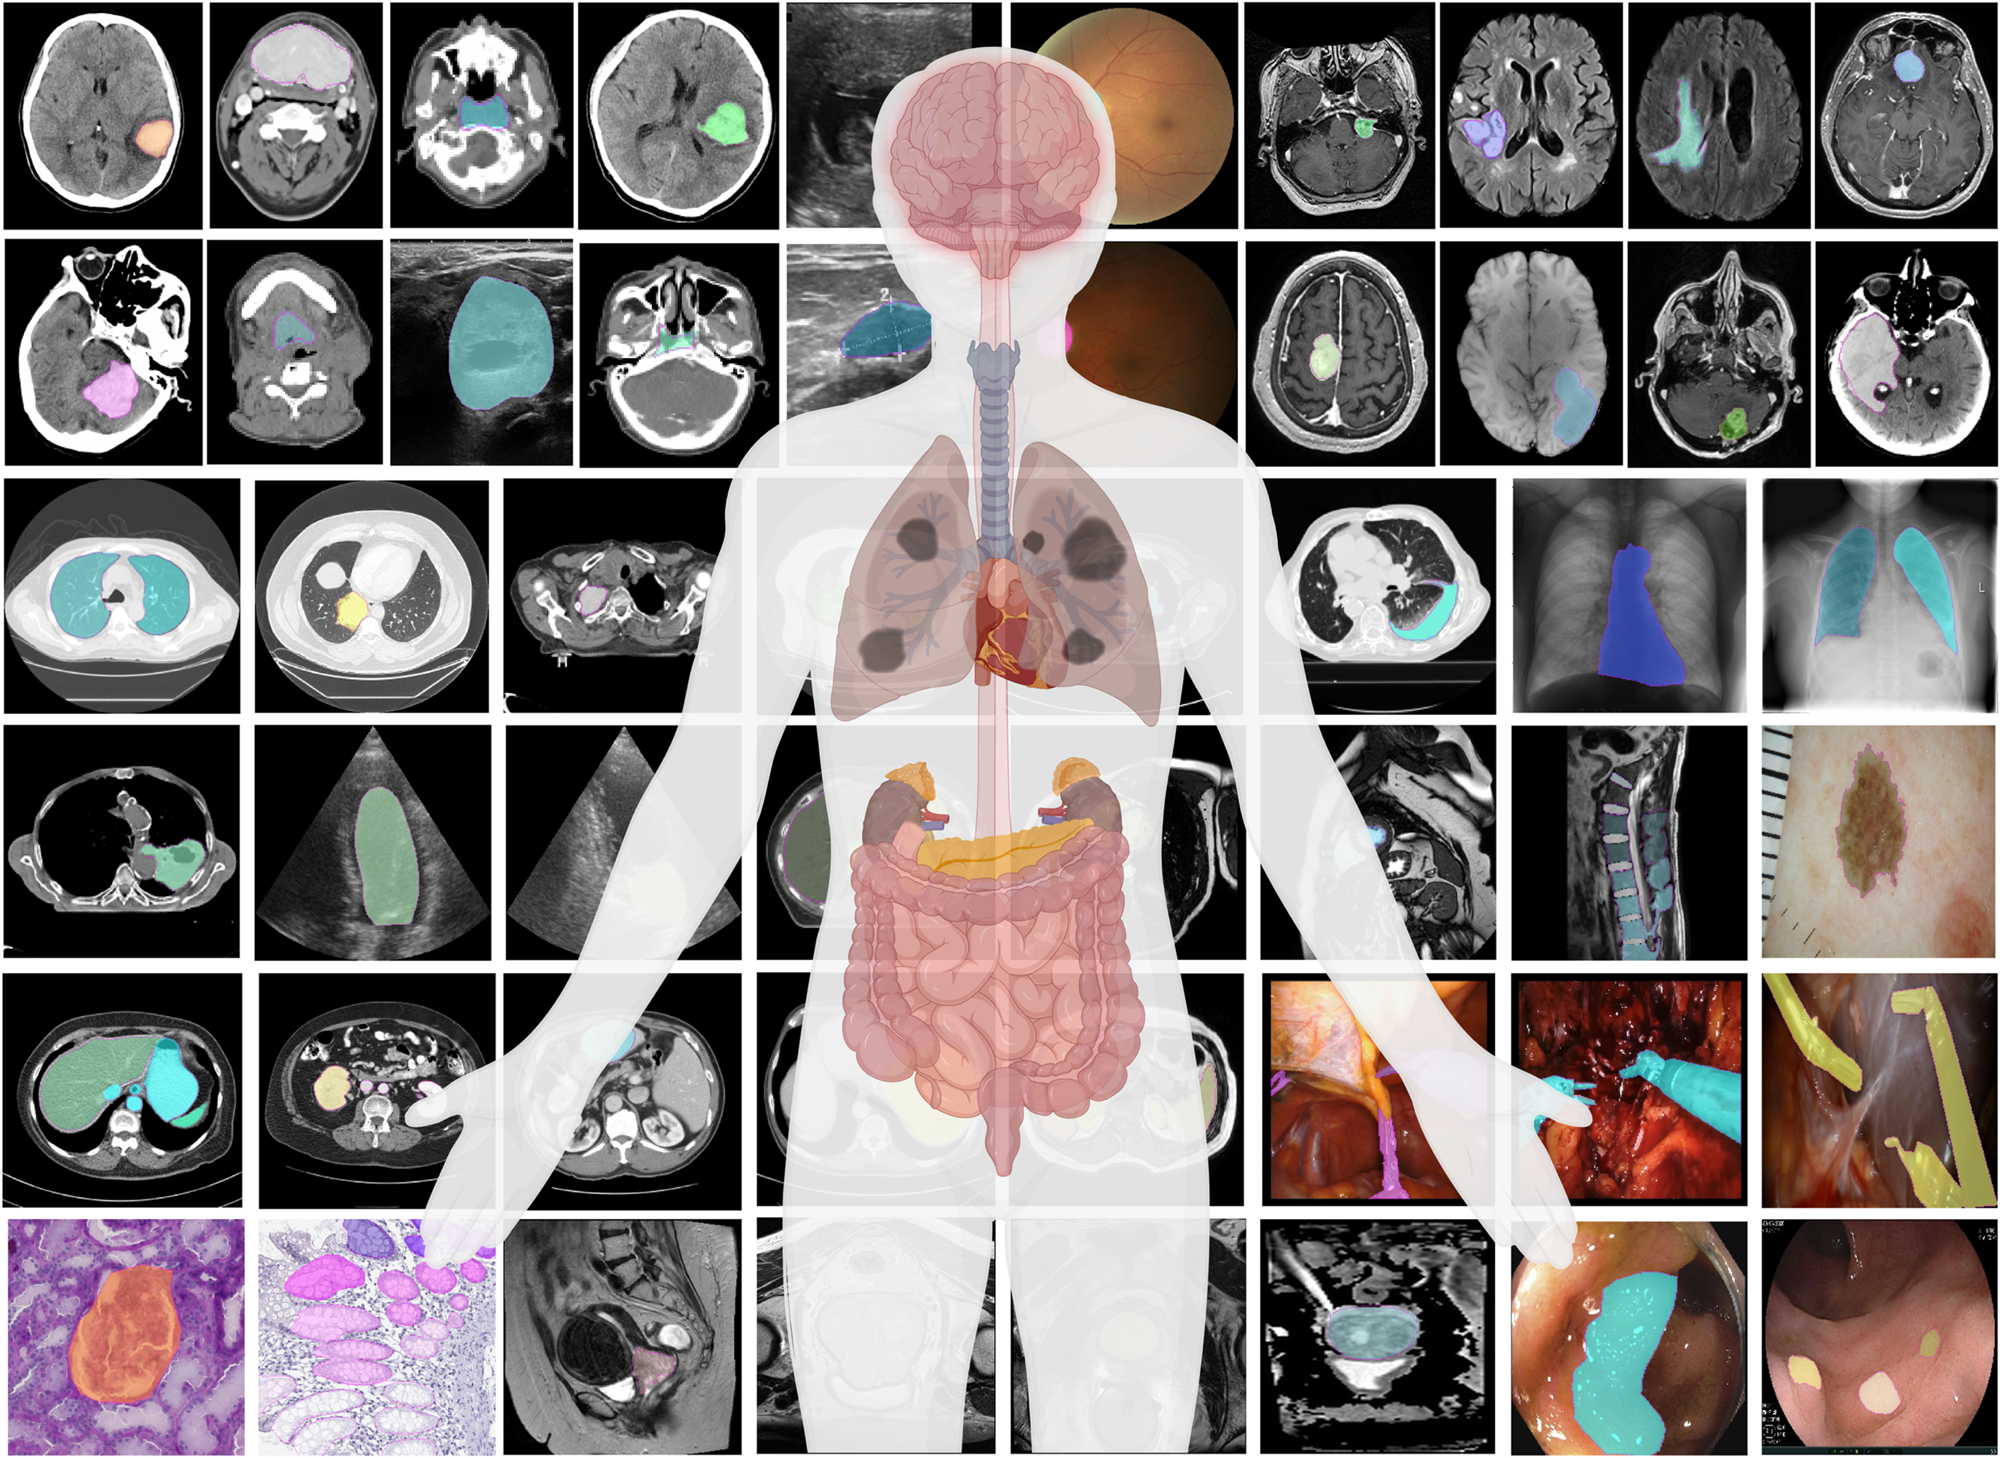

6. Image Segmentation¶

Task: Classify every pixel in an image - the most detailed form of visual understanding

Medical Applications:

- Organ segmentation for surgical planning and volume measurement

- Tumor delineation for treatment planning and monitoring

- Cell segmentation in microscopy images

- Tissue type differentiation (gray/white matter, CSF)

Types:

- Semantic Segmentation: Labels all pixels of the same class identically

- Instance Segmentation: Distinguishes between different instances of the same class

C. Object Detection¶

Task: Identify what objects are in an image AND where they are located

- Nodule detection in lung scans

- Cell counting in microscopy

- Surgical instrument tracking

- Polyp detection in colonoscopy